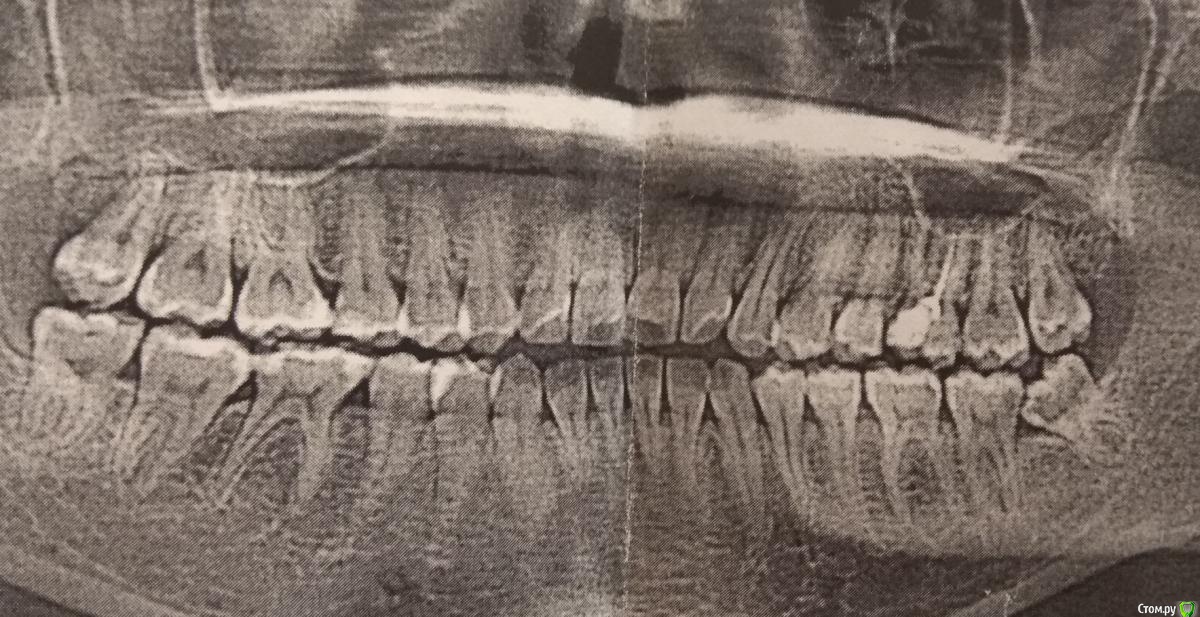

IAmValeria Опубликовано 12 апреля, 2020 Поделиться Опубликовано 12 апреля, 2020 Здравствуйте. Месяц назад мне удалили под местной анестезией восьмёрку нижнюю слева, которая упиралась в семёрку. И в восьмёрке и в семёрке был кариес. Практически сразу после удаления заболели практически все зубы с этой стороны внизу, с концентрацией боли в клыке. Потом через 2 недели вылечили семерку, тоже под местной анестезией, анестезия ещё была в самом разгаре, а клыки заболели все сильнее. То есть после анестезии стало ещё хуже, просто невыносимо. Теперь мучают каждый день периодические боли, могут длиться 5 минут, могут несколько часов. Болят все зубы слева внизу, иногда и наверху тоже. В моменты приступов до зубов невозможно дотрагиваться. Подскажите, пожалуйста, что это может быть? Я уже измучилась. Ходила к врачам, ничего плохого не видят. На данный момент предположили, что могли задеть нерв в момент удаления, но что-то я слабо в это верю. Пью фенлипсин уже 5 дней, улучшений нет. Я очень устала от боли. Прилагаю свои снимки до и после удаления. Прошу, помогите. Ссылка на комментарий

IAmValeria Опубликовано 12 апреля, 2020 Автор Поделиться Опубликовано 12 апреля, 2020 что делали с 7 зубом? Есть актуальный снимок?Вот снимок, буквально пару дней назад сделан. В семёрке лечили кариес. Ссылка на комментарий

St. Опубликовано 13 апреля, 2020 Поделиться Опубликовано 13 апреля, 2020 Мог ли при удалении восьмёрки остаться корень? По снимку после удаления все ок. доктор долго не могла найти второй корень в ране, потом отправила на рентген, Зубы мудрости иногда очень коварны и в плане обезболивания и в плане удаления. Ссылка на комментарий

Zlata-doctor Опубликовано 13 апреля, 2020 Поделиться Опубликовано 13 апреля, 2020 Валерия, добрый день! Я очень Вам сочувствую.Я думаю,что у вас скоро все должно пойти на улучшение.Я считаю, что причина болей не в конкретном зубе. Во-первых, слишком долго все это продолжается. Обычно осложненный кариес с интенсивными болями довольно быстро ( за несколько дней) куда-то разрешается: или проходит боль, то есть переходит в хроническую фазу, или обостряется с отеком и даже гноем итд. У вас более месяца ничего этого нет. Поэтому можно думать о причине непосредственно в области удаленного зуба. Тем более, что был удален зуб мудрости, который чаще всего и дает такие осложнения. Поэтому я бы очень осторожно предпринимала попытки лечить другие зубы в этой области!!! Это необоснованно!!Честно говоря, ваш снимок не показывает ничего подозрительного. Я думаю, что у вас имеется неврологическое поражение. К сожалению, такое состояние не проходит быстро и очень мучительно. Также нет достоверных данных, что витаминные препараты типа Мильгаммы или какие-то БАДы ускоряют процесс восстановления. Поэтому в такой ситуации остается ждать и обезболиваться. Препарат выбора здесь Габапентин , Лирика-неврологические препараты, которые должен назначить только невролог. Обратитесь к грамотному неврологу и выздоравливайте, пожалуйста. 1 Ссылка на комментарий